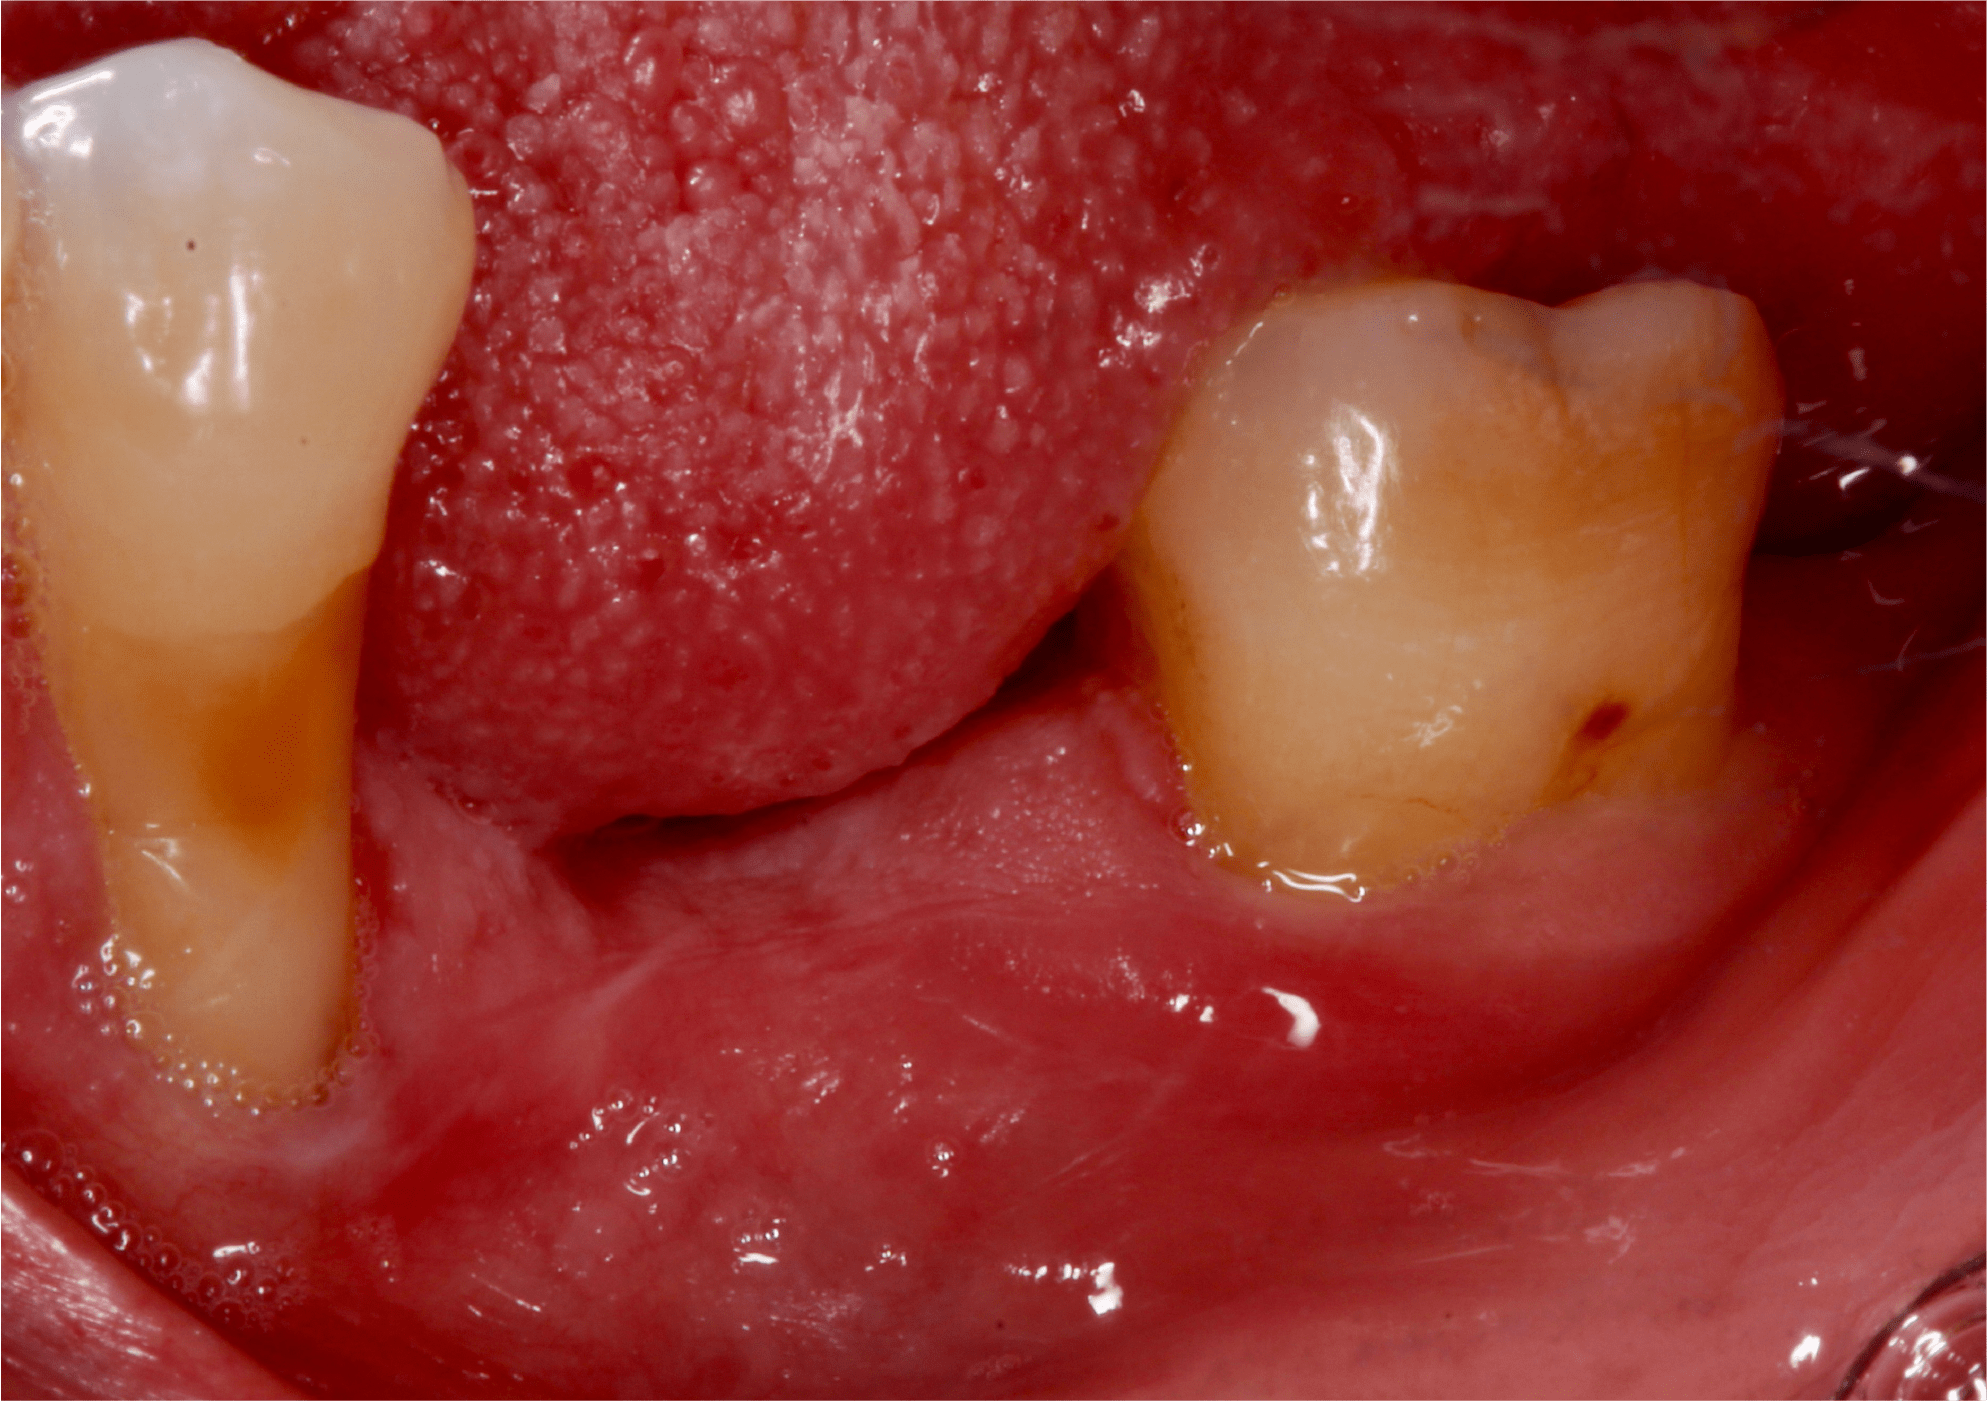

Paciente femenino de 57 años, ama de casa, originaria de Arandas, Jalisco se presenta al departamento de Periodoncia e Implantología derivada por el departamento de Prostodoncia. El motivo de su consulta fue “Quiero reponer mis dientes restantes” como resultado de la anamnesis presenta un buen estado de salud general aparente, sin antecedentes patológicos. (Fig. 1).

La examinación clínica reveló recesiones en múltiples órganos dentales y dos brechas edéntulas en la mandíbula correspondientes a los órganos dentales “36” y “46” las cuales fueron perdidas debido a caries (Fig. 2 y 3).

También se pudo apreciar que la paciente presentaba un fenotipo delgado y al medir la cantidad de encía queratinizada se observo una banda angosta de la misma, aproximadamente de 1 – 2 mm. (Fig. 4).

Fig. 1

Fig. 2

Fig. 3

Fig. 4